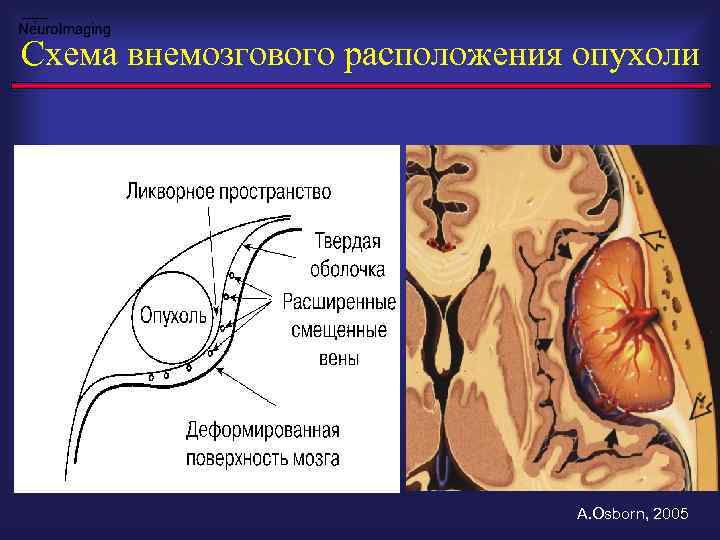

Схема внемозгового расположения опухоли A. Osborn, 2005

Внемозговое расположение: ликворная щель, дислокация мозга, периф. сосуды